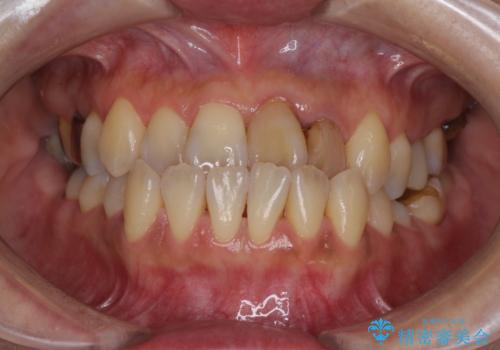

[MTMを行い歯の神経を保存] 歯周補綴ブリッジ